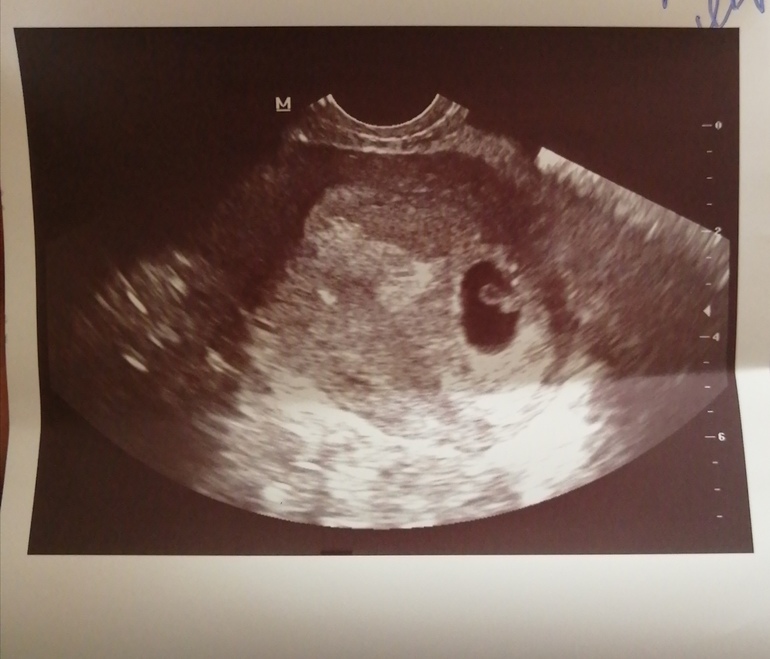

Токсикоз. Гестоз. ОтекиДевочки срок 6-7 недель. Сегодня была на узи ктр 6+3.все хорошо. Сердцебиение 118. С сыном было 160.Хочется дочу❤️🥰Единственное мучает сильный токсикоз неделю уже-(((что не съем рвёт. До желчи. Сил нету🤮